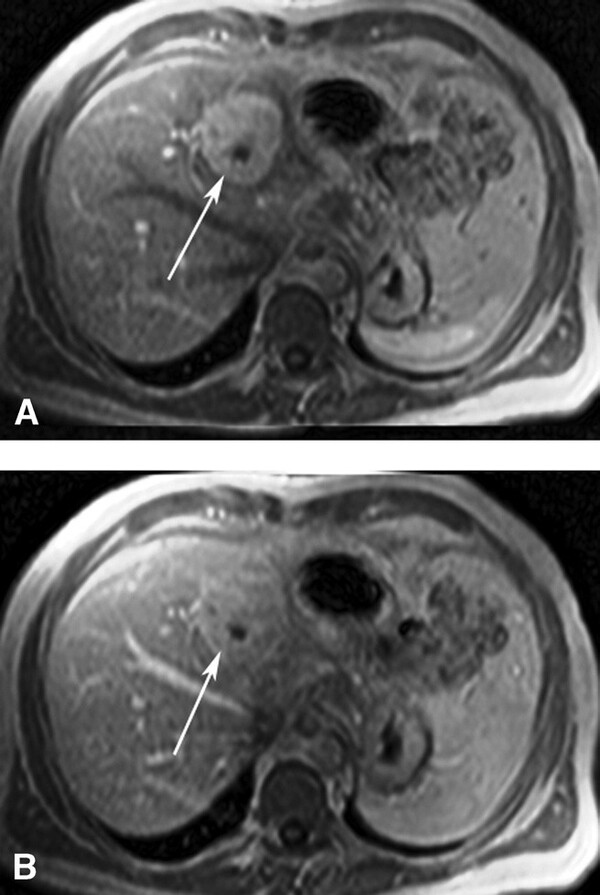

Hemangioma là u gan lành tính thường gặp nhất. Hemangioma thường gặp ở phụ nữ trẻ và 15-20% nhiều ổ. Mô học cho thấy một loạt các hồ máu và kênh mạch, các tổn thương lớn hơn tạo ra các vùng huyết khối và xơ. Siêu âm thấy một khối tăng âm, đồng nhất, giới hạn rõ, tăng âm phía sau yếu (Hình 1). Các tổn thương lớn hơn (>6cm) có thể không đồng nhất và giảm âm do huyết khối, hoại tử và thoái hóa nang. Các dấu hiệu CT cản quang gồm tăng quang dạng nốt ngoại vi ở thì động mạch với lấp đầy hướng tâm dần trong tổn thương ở thì tĩnh mạch cửa và thì muộn (hình 2). Vôi tĩnh mạch (phlebolith) có thể thấy trong tổn thương ở 15-20% trường hợp (Hình 2). MRI cho thấy tăng tín hiệu trung bình trên T2W, thường ít hơn so với nang đơn thuần, tín hiệu thấp trên T1W. MRI sau tiêm thuốc cho thấy bắt thuốc dạng nốt gián đoạn phía ngoại vi ở thì động mạch, đó là đặc điểm điển hình của hemangioma (Hình 3). MRI thì tĩnh mạch và thì muộn có thể thấy các nốt bắt thuốc lớn dần và hợp lưu với lấp dầy trung tâm ở các mức độ khác nhau tương tự như CT.

Hình 3. Hemangioma gan kinh điển. Tổn thương (mũi tên) tăng tín hiệu trên T2W FS single-shot fast spin-echo(SSFSE) (A). Có bắt thuốc dạng nốt ngoại vi (mũi tên) ở thì động mạch (B) và lấp dần vào trung tâm (mũi tên) ở thì tĩnh mạch cửa (C) và thì muộn (D) trên hình T1W 3D GRE.